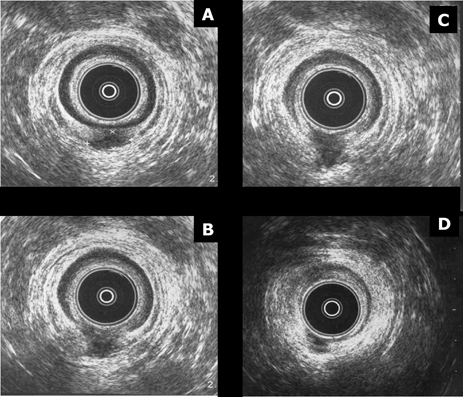

Imágenes de una misma paciente con absceso interesfinteriano posterior (x). De “A” a “D” las imágenes son secuenciales y pasamos de tercio medio a tercio inferior de ano.